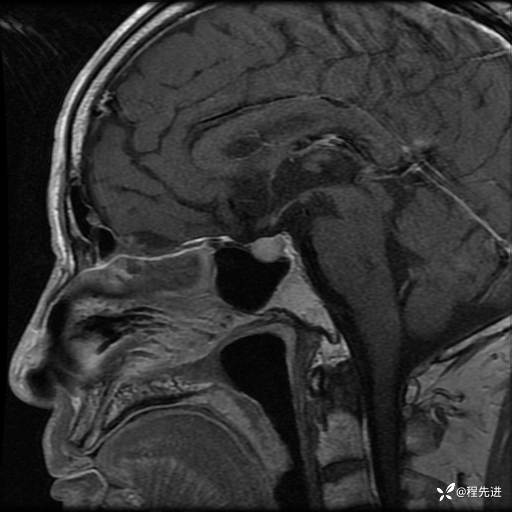

MRI平扫+增强:

T1: